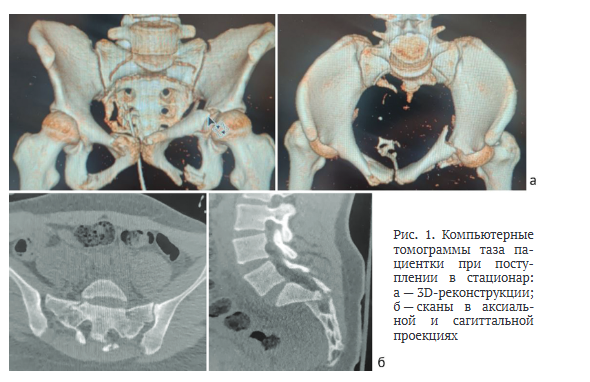

В результате КТ таза при поступлении выявлены: оскольчатый нестабильный перелом крестца со смещением; переломы правой лонной, седалищных костей и левой вертлужной впадины со смещением (рис. 1).